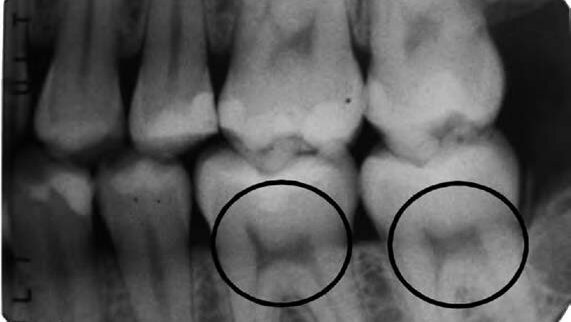

Η πολφική μορφολογία σε ένα υγιές δόντι προσομοιάζει ένα τόξο που στην κορυφή εμφανίζει δύο προεκτάσεις σαν ''αυτιά γάτας'', αλλά σε έναν άνθρωπο με σοβαρή έλλειψη βιταμίνης D είναι ασύμμετρο και περιορισμένο, μοιάζοντας περισσότερο με το προφίλ μίας καρέκλας με σκληρή πλάτη.

Η έρευνα των D'Ortenzio, Brickley στο παρελθόν είχε υποδείξει ένα τέτοιο αναγνωρίσιμο μοτίβο και η εξέτασή τους τόσο παλαιότερων όσο και σύγχρονων δοντιών απέδειξε πως οι ακτινογραφικές εικόνες συμβαδίζουν και είναι αξιόπιστοι δείκτες της προηγούμενης έλλειψης.

Για να αποφευχθεί η απώλεια πολύτιμων δειγμάτων, οι ερευνητές αναζήτησαν έναν τρόπο να απομονώσουν δόντια για περαιτέρω διερεύνηση. Χρησιμοποιώντας ακτινογραφίες για να μελετήσουν την άμεσα παρατηρήσιμη μορφολογία των πολφικών κεράτων, οι ερευνητές βρήκαν ένα σταθερό και αναγνωρίσιμο τρόπο που θα μπορούσε να βοηθήσει τόσο στις μελέτες αρχαιολογικών δοντιών, καθώς και σε ανθρώπους που μπορεί να μη συνειδητοποιούν πως εμφανίζουν έλλειψη βιταμίνης D.